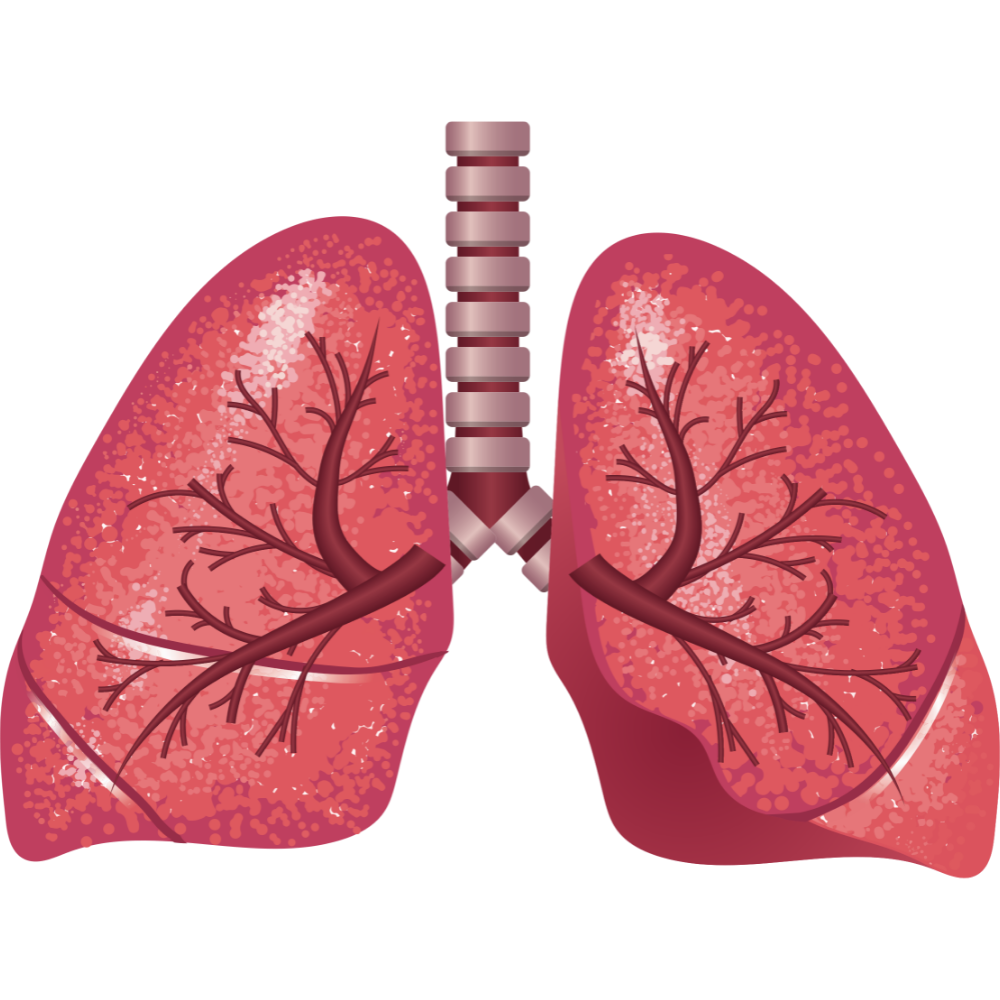

Здоровые Легкие Картинки

Здоровые Легкие Картинки 117 фото